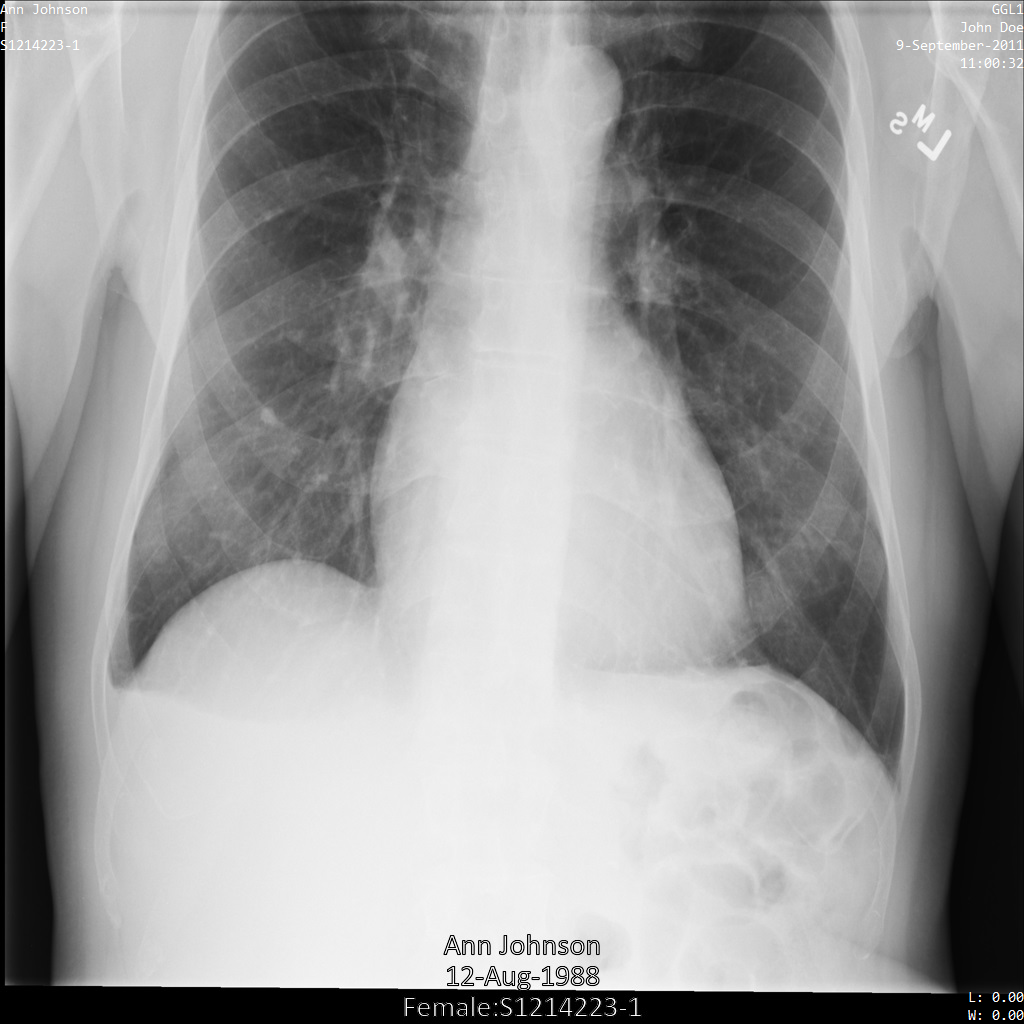

Nachdem Sie das Bild mit dem Tag-FilterprofilATTRIBUTE_CONFIDENTIALITY_BASIC_PROFILE an die Cloud Healthcare API gesendet haben, wird das Bild wie folgt angezeigt: Während die in den oberen Ecken des Bildes angezeigten Metadaten entfernt wurden, bleibt die eingebrannte PHI unten im Bild erhalten.

Informationen zum Entfernen des eingebrannten Texts finden Sie unter Eingebrannten Text aus Bildern entfernen.